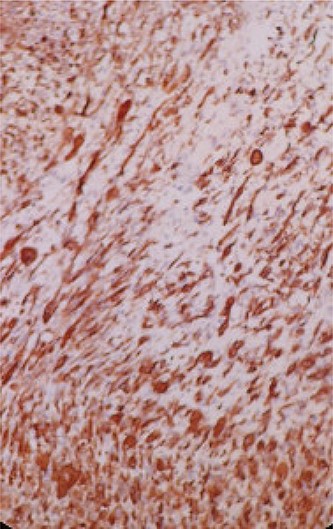

A 68-year-old man, diabetic, presented for terminal hematuria associated with pelvic pain. His physical examination was normal. Ultrasonography and chest and abdominopelvic computed tomography (CT) scan revealed a urinary bladder tumor of 5 × 5 cm over the dome and the anterior wall with normal upper tract (Fig. 1). Cystoscopic exploration revealed a solid lesion in the anterior wall and the dome with a large base. The patient underwent a complete and deep transurethral resection of the bladder tumor. Anatomopathological examination showed a carcinosarcoma appearance with a rhabdomyoblastic differentiation (Figs 2 and 3). A chest and abdominopelvic CT scan, with intravenous administration of contrast medium (CT), did not show pelvic lymphadenopathy or secondary location. Radical surgery was then decided without neoadjuvant therapy. Cyst prostatectomy with Bricker diversion and lymph node dissection was performed. The postoperative course was uneventful. The pathological examination of the surgical specimen confirms the diagnosis of a bladder carcinosarcoma with a rhabdomyoblastic differentiation. After 12 months of clinical and radiological check-ups, there was no functional complaint or any sign of reoccurrence.

Immunohistochemical (IHC) study shows the positivity of rhabdomyoblastic cells to the anti-desmin antibody (IHC * 20).